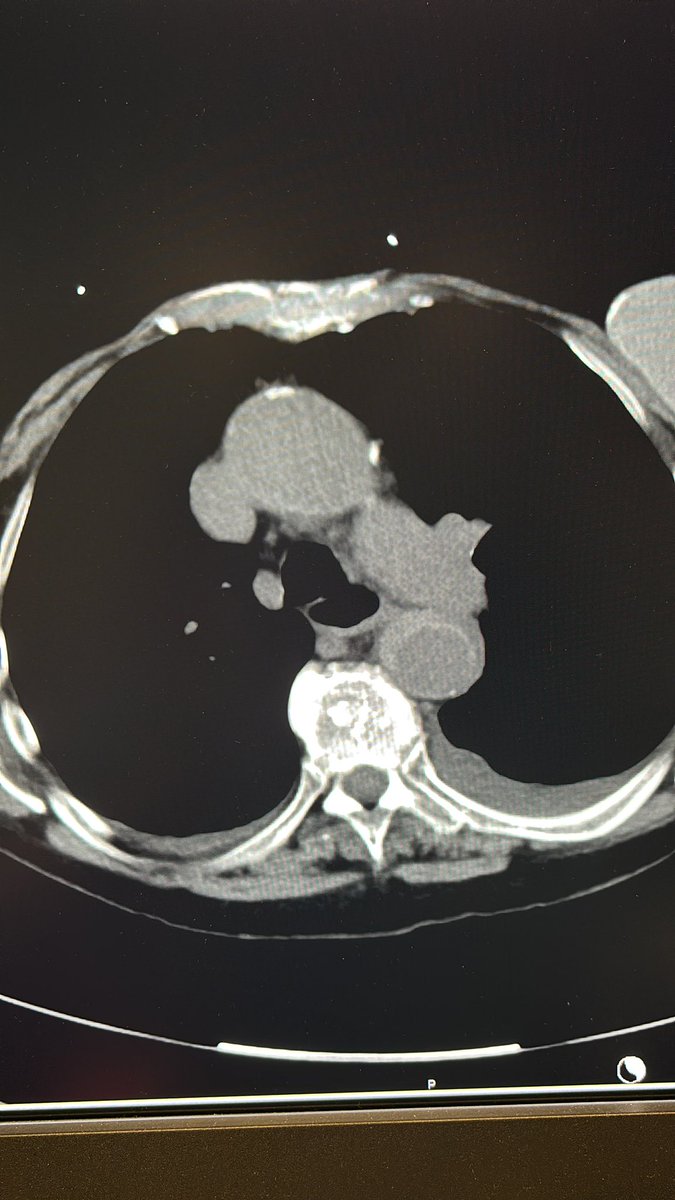

What better way to start holiday weekend call than a TIPS PR

Bleeding tips:

22 mins from lido to pressure, single stick w/ #ScorpionX

Gradient 27>8mmHg, 8cm Viatorr

#ICETIPS @WLGore @ArgonMedical

Props again to @tarheeldylan and @_backtable (episode 455 for basic technique)